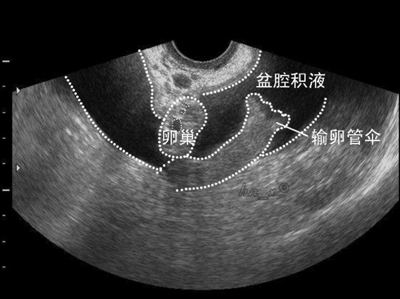

盆腔积液